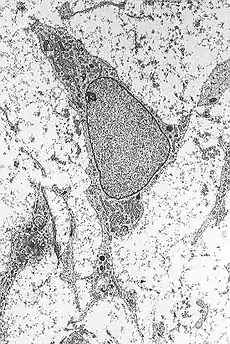

The proposed method includes the conversion of mesenchymal stem cells (cells usually intended for generation of bones and adipose tissue) into neurons after a short exposure to retinoic acid diluted in ethanol.[15] The therapy consists in removing cells from the bone marrow of patients, their in vitro manipulation (incubation of stem cells for 2 hours in an 18 micromolar solution of retinoic acid), and finally their infusion into patients themselves.[16]